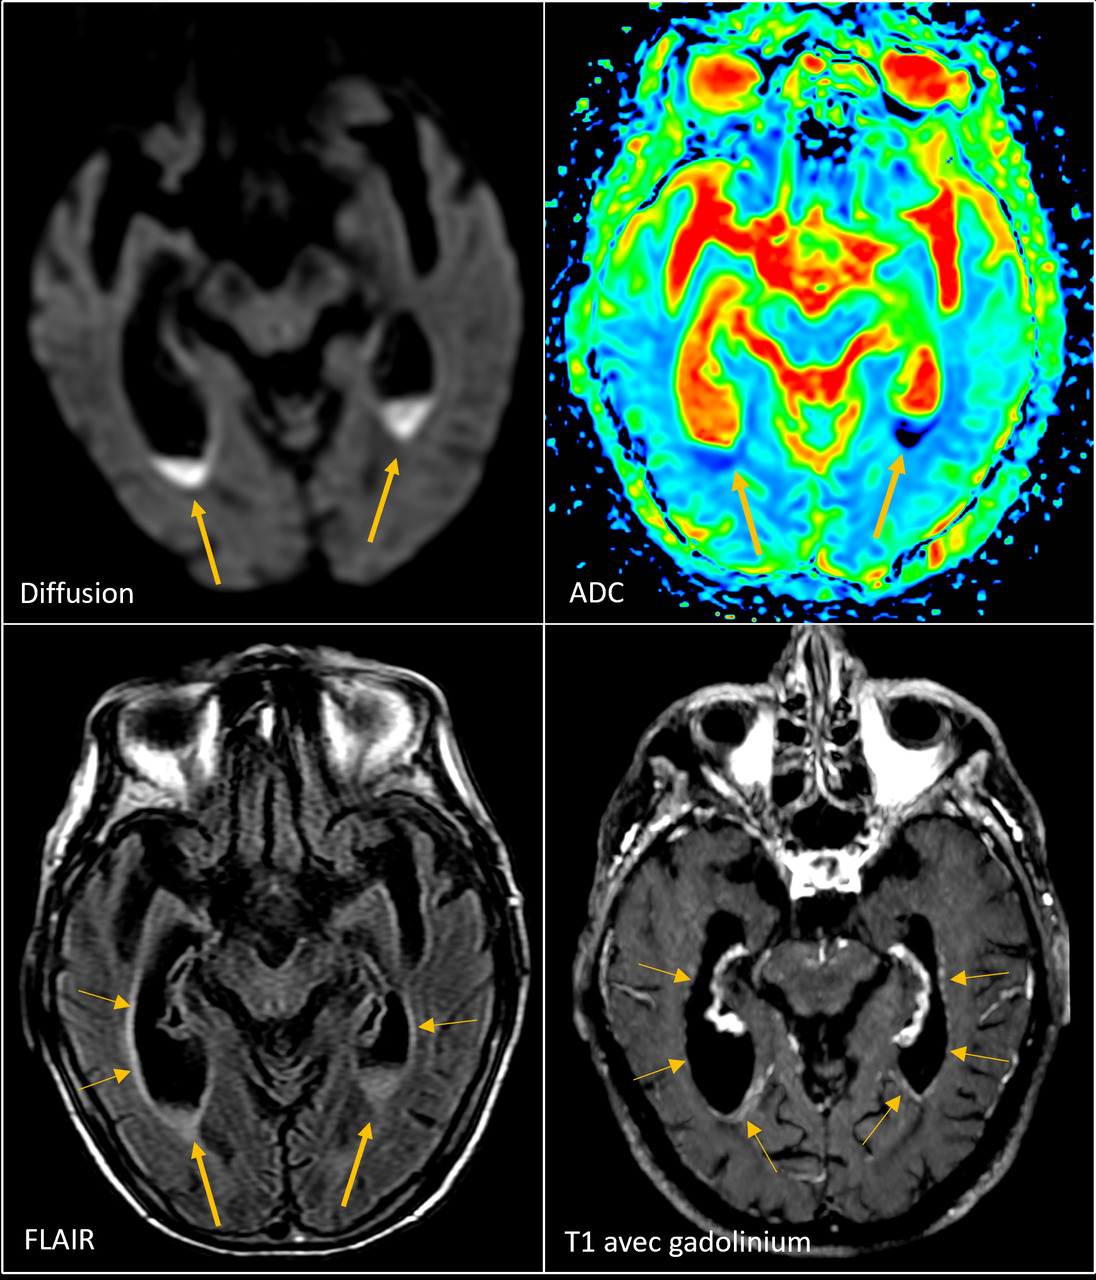

Une patiente âgée de 90 ans vivant seule chez elle, avec la visite d’aides à domicile, est hospitalisée pour une asthénie sévère associée à un syndrome confusionnel fébrile évoluant depuis quelques jours, sans point d’appel clinique. Elle est en bon état général et est sous valsartan pour une hypertension artérielle. L’examen clinique ne retrouve aucune anomalie en dehors d’une confusion fébrile sans syndrome méningé ni signe de localisation. Les hémocultures sont stériles. La protéine C-réactive (CRP) est à 126 mg, avec une hyperleucocytose à polynucléaires neutrophiles à 13 000/mm3. Le reste du bilan biologique est normal. Une ponction lombaire est réalisée en urgence  ; elle montre un liquide céphalorachidien (LCR) citrin (fig. 1) avec une protéinorachie à 3,29 g/L, une hypoglycorachie à 450 leucocytes/mm3 (36 % de polynucléaires, 75  % de lymphocytes). L’examen direct du LCR révèle des bacilles à Gram positif et la culture confirme l’identification de Listeria monocytogenes sensible à l’amoxicilline et au cotrimoxazole.  Dès les résultats de la ponction lombaire, la patiente a été mise sous amoxicilline à la dose de 200 mg/kg/24 h et de la gentamicine à 5 mg/kg/24 h a été ajoutée pour cinq jours. L’imagerie par résonance magnétique (IRM) [fig. 2] met en évidence plusieurs abcès (protubérance, cervelet) et une ventriculite bilatérale avec pus intraventriculaire (fig. 3). La patiente n’était pas immunodéprimée. La déclaration obligatoire a été effectuée. L’enquête de l’agence régionale de santé (ARS) n’a pas retrouvé de cas groupés dans l’entourage. Après six semaines d’antibiothérapie par amoxicilline intraveineuse à haute dose, la patiente a recouvré une conscience normale, sans séquelle neurologique clinique apparente, et une autonomie qui ont permis le retour à domicile.

La localisation méningée1,2 est associée dans près de la moitié des cas à des signes d’encéphalite diffuse avec des abcès intracérébraux localisés de façon prédo­minante au rhombencéphale. Des abcès nécrotiques coalescents et multiples apparaissent, entraînant des pertes de substances importantes du tissu nerveux.